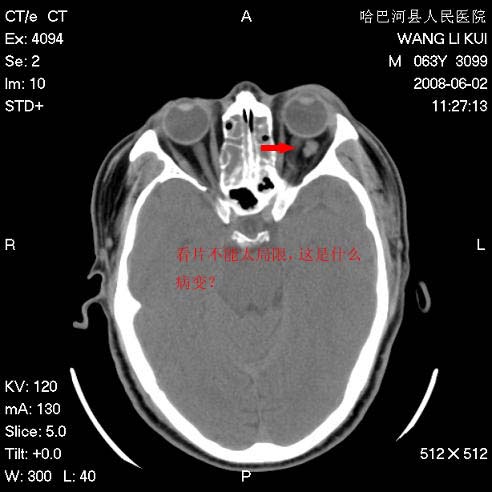

标题: CT13803:反复性鼻塞、流涕一年余 [打印本页]

标题: CT13803:反复性鼻塞、流涕一年余

副鼻窦炎,右上额窦积脓。左眼肌锥内见致密影,视神經受压

全组副鼻窦炎 肌锥内高密度灶。建议进一步检察检查

1、全组副鼻窦炎。

2、左眼眶肌锥内病变,小血管瘤?建议增强。

2、左眼眶肌锥内病变,建议增强

1)全副鼻窦炎(左侧上颌窦黏膜下囊肿或息肉)。2)左眼眶肌锥内不规则小结节状软组织密度影;考虑为小血管瘤可能。建议行ct增强扫描检查。

全组副鼻窦炎,左侧肌锥内不规则形软组织肿块影,与眼外肌密度相当,左侧视神经受压,肿块与视神经及眼外肌分界清晰,眼外肌无增粗,眶壁无破坏,球后脂肪间隙不模糊,考虑良性改变,小血管瘤或神经源性肿瘤可能,建议增强扫描。

谢谢,增强扫描做了,眶内病灶与海绵窦同步明显强化,血管瘤